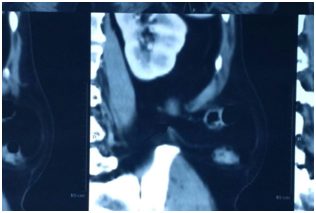

A 50 year-old male presented with progressively enlarging swelling in the right loin. There was no history of trauma, fever, weight loss and any associated bowel or urinary complaint. There was no significant past medical or surgical history. On examination there was a 5cm× 4cm partially reducible non tender mass located in the inferior lumbar triangle which was prominent during Valsalvamaneuver. Computer tomography (CT) scan was done which confirmed the diagnosis of inferior lumbar hernia (Figure 1). Open repair done with meshplasty (Figure 2).

Figure 1 CT scan showing hernia.